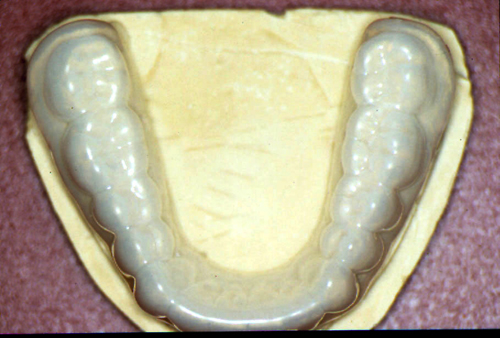

ABSTRACT El Bruxismo es una entidad patológica en la que concurren diferentes factores. Entre ellos el stress que conlleva consigo la vida moderna, constituye el Factor Predisponente sobre el que se ha abundado en innumerables tratamientos de tipo general, actuando sobre la psiquis y el comportamiento del individuo, ya sea con fármacos o bien mediante medios psicológicos. Sin embargo, como tantos desequilibrios provocados por el stress, confluyen siempre con un Factor Desencadenante, que en el caso del Bruxismo se encuentra en las desarmonías entre los componentes varios del Sistema Estomatognático. DESARROLLO Paciente varón, de 43 años, constitución atlética. A la inspección se observan desgastes oclusales que alcanzan la calidad de Facetas Parafuncionales, con dentina expuesta y empastes totalmente gastados y evidentes signos de falta de Disclusión Canina de ambos lados. Sobre dicho montaje se realiza un Encerado Progresivo de Diagnóstico, aportando en el mismo los elementos necesarios para obtener todos los principios básicos de una Oclusión Orgánica. FIG. 6 a 24 Una vez aprobado el fisiologismo de la oclusión en el articulador, se reproducen modelos de yeso con la nueva situación, y se estampa un SET UP en cada maxilar. FIG. 25/26 Procedemos entonces al tallado de las piezas correspondientes a la Guía Anterior, y rebasamos los estampados, creando en boca una nueva situación desoclusiva, que permanece en boca durante los pocos días que transcurren entre la primera y segunda visita de trabajo. FIG. 27/33 Ya abordando en esta segunda visita los sectores posteriores, tanto superiores como inferiores, tallamos siempre de manera supragingival, destacando la importancia vital de la forma obtenida en las provisionales, a las que abrimos plenamente las troneras para lograr una correcta higiene. FIG.34 a 43 FIG. 44 a 52 Efectuados los colados en oro y probados en boca, en el laboratorio se confecciona el bizcochado de la nueva Guía Anterior, la que puede o no copiarse de la Guía Anterior provisional, mediante la técnica denominada Trayectoria Funcionalmente Generada, que consiste en realizar en la platina del articulador un registro estereográfico sobre acrílico Duralay en polimerización. FIG. 57/58 Ajustados todos los detalles mediante esta técnica, se instala en boca en forma Provisional y se deja funcionando una semana o dos, al cabo de las cuales se chequean las disclusiones , los ajustes, la eficacia masticatoria, la carencia de sintomatología articular y muscular. FIG.59 a 63 PIE DE FOTO FIG.9 OBTENCIÓN DE LA GUÍA ANTERIOR FIG.10 Y 11 PITOMBOS. ALINEAC. TRIDIMENSIONAL FIG.12 PITOMBOS. DISCLUSIÓN DER. FIG.13 PITOMBOS. DISCLUSIÓN IZQ. FIG.14 WILSON INF. FIG.15 WILSON SUP. FIG.16 BOCA DE PEZ INF. FIG.17 BOCA DE PEZ SUP. FIG.18 VISTA OCLUSAL FIG.19 O.R.C. FIG.20 DISCLUSIÓN DERECHA FIG.21 CRESTAS TRIANG. INT. FIG.22 CRESTAS TRIANG. INT. FIG.23 CRESTAS TRIANG. INT. FIG 24 CRESTAS TRIANG. INT. FIG.59 DISCLUSIÓN IZQ. FIG.60 DISCLUSION IZQ. FIG.61 DISCLUSIÓN DER. FIG.62 DISCLUSION DER. FIG. 63 AJUSTE PERIFÉRICO